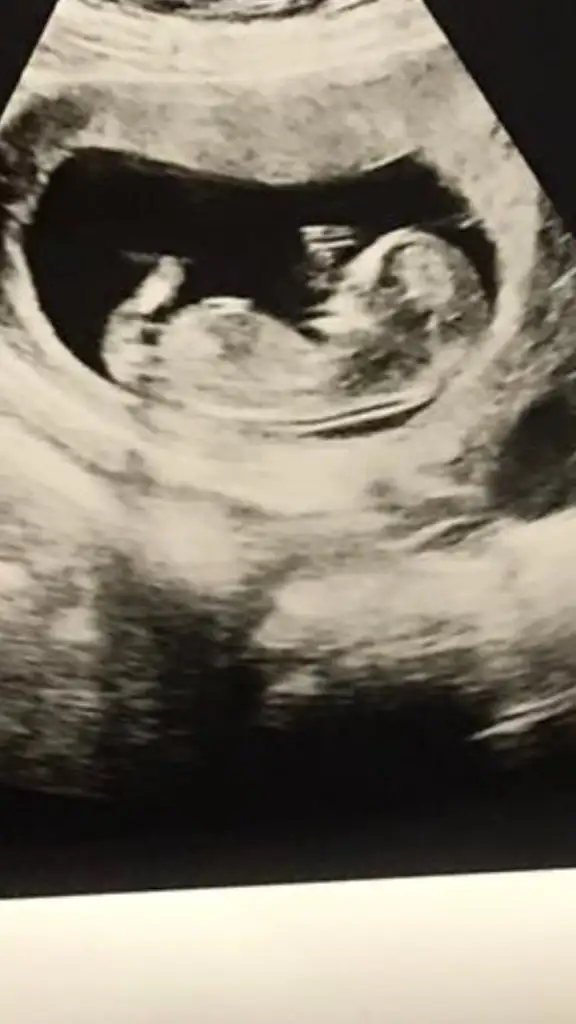

Ikra meyra Ikra meyra canım ilk çocuğumun cinsiyetini bilmiştin buna da bakabilir misin? Şimdiden çook teşekkür ederim🥰

Eklentiler

• IMG-20210906-WA0004.webp

IMG-20210906-WA0004.webp

17,8 KB · Görüntüleme: 89

• IMG-20210906-WA0005.webp

IMG-20210906-WA0005.webp

23,6 KB · Görüntüleme: 107

Merhaba canım doktor kordon mu erkek mi karar veremedi 2 hafta sonra bi daha gel dedi başta erkek diyecektim sonra kordon olduğunu anladım dedi kesin bişey diyemiyorum dedi sen bi bakabilir misin 🥺🙏🏻🙏🏻♥️♥️♥️ Ikra meyra Ikra meyra Ikra meyra Ikra meyra